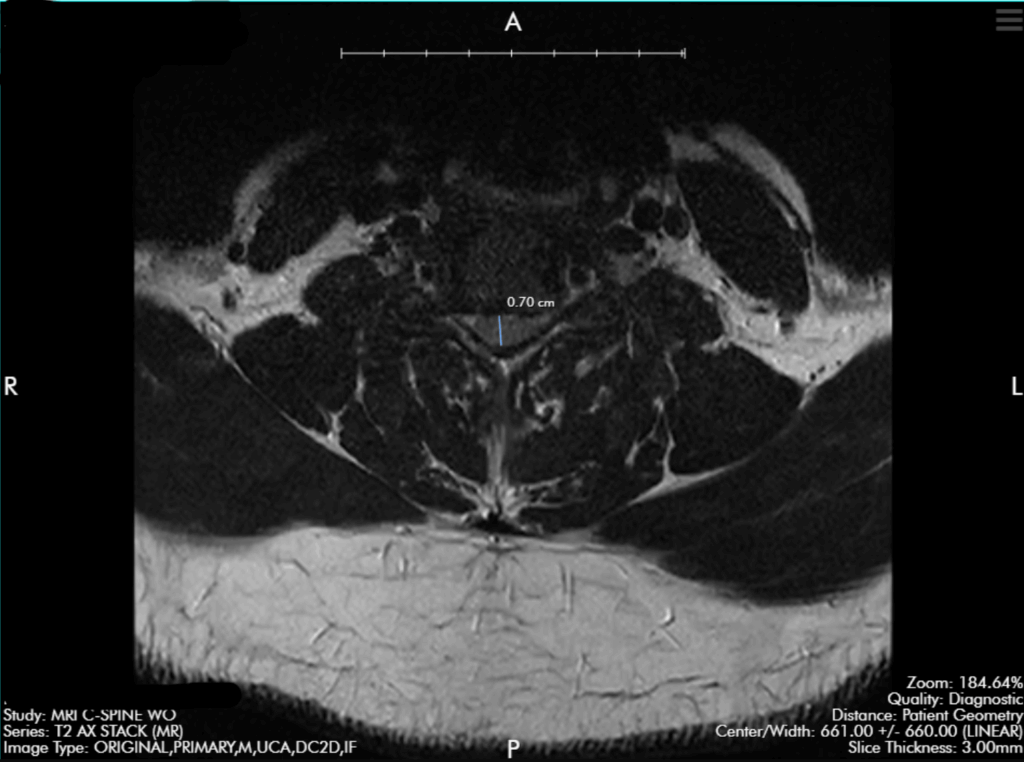

Anterior Cervical Disc Replacement